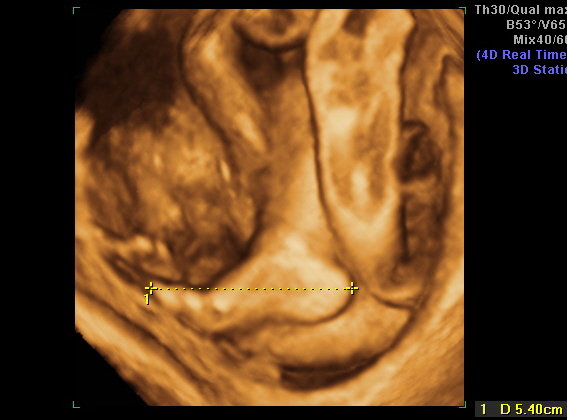

A mi kis álmodozónk